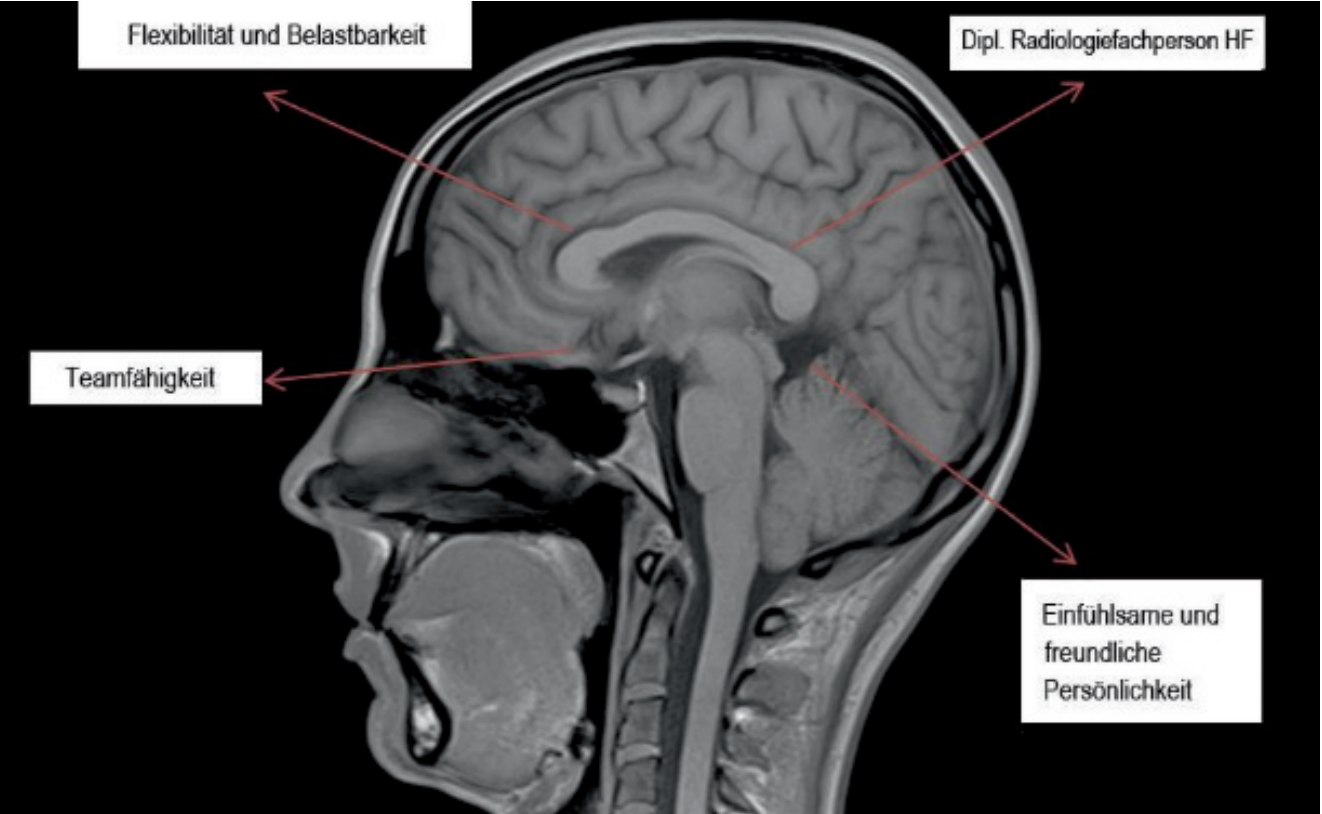

DIPL. RADIOLOGIEFACHPERSON HF 60% bis 100%

Zur Unterstützung unseres Teams an den Standorten Dielsdorf und Kloten suchen wir eine Radiologiefachperson (MTRA). Wir bieten geregelte Arbeitszeiten ohne Wochenend- oder Nachtdienste. 25 Tage Ferien, ab 50 Jahren 30 Tage Ferien. Diverse Weiterbildungsmöglichkeiten und Unterstützung bei Ihrem Umzug in die Schweiz. Interesse? Dann würden wir uns sehr über Ihre Bewerbung freuen.